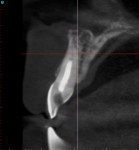

When a tooth is fractured or requires extraction, a dental implant is the only treatment option that will restore the root of the tooth, which can provide support for a new clinical crown. A CBCT scan can provide an accurate 3D-reconstructed volume as an aid in planning for an implant-supported restoration (Figure 1). The cross-sectional image reveals the precise location of the root within the alveolus, provides information on bone density, and shows that the tooth had previous root canal therapy (Figure 2). The axial image is important to help determine the morphology of the tooth root based upon the inferior-superior location of the slice (Figure 3). Depending on the interactive treatment planning software, the use of realistic manufacturer-specific virtual implants of known length and diameter can be simulated within the receptor site (Figure 4). The yellow projection is a helpful tool to aid the clinician in establishing the proper trajectory of the implant within the cross-sectional image and in relation to the desired restorative option (ie, screw- or cement-retained). It should be noted that this is only one slice, and that the final positioning of the implant should be determined only after all views have been considered.